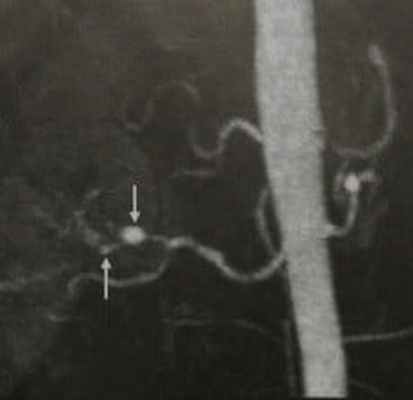

■ медиальный тип ФМД (тип I) встречается наиболее часто: он характеризуется трансформацией гладкомышечных клеток медии в фибробласты с одновременным накоплением пучков эластических волокон на границе с адвентицией, приводящим к образованию «перетяжек»; для этого типа присущ ангиографический паттерн «нить бусин» (string of beads) - чередование сегментарных коротких стенозов артерии с расширениями - этот признак ряд авторов считают маркером ФМД медиального типа, поскольку для других типов ФМД этот признак не является характерным;

Принципы диагностики. Постановка диагноза начинается с тщательного сбора анамнеза. Важным является выяснение наличия у родственников данной патологии. Но так как специфических, однозначно указывающих на заболевание, признаков нет, то ведущими методами диагностики считаются дуплексное сканирование [подробнее] сосудов и ангиография (cелективная дигитальная субтракционная ангиография [подробнее]). Ангиографию называют «золотым стандартом» при диагностике ФМД. Рентгенологическое исследование с введением контрастного вещества позволяет достоверно выявить характерные сосудистые изменения. Так как при дисплазии происходит фрагментарное сужение просвета артерии, часто чередующееся с аневризматическими расширениями, то рентгенологическое изображение напоминает бусы, или четки. Для большей информативности обследование проводят в двух проекциях (также информативны: КТ-ангиография, МРТ-ангиография). Дуплексное сканирование, сочетающее УЗИ с допплеровским исследованием, подтверждает диагноз. Оно наглядно демонстрирует диспластические изменения структуры сосудов, степень сужения просвета, дает возможность оценить кровоток и измерить его скорость.

В крупных артериях также встречается фиброзно-мышечная дисплазия. Причина ее неизвестна. Заболевание характеризуется множественными зонами эксцентрического сужения артерии, чередующихся с сегментарными дилятациями. На ангиограмме пораженные сосуды выглядят в виде «стеклянных бус». Редко бывает отдельный стеноз. Более 90% больных с фиброзно-мышечной дисплазией составляют женщины. Данное заболевание чаще поражает почечные артерии. В 80% случаев поражается правая почечная артерия. Далее следуют сонные и подвздошные артерии. Брыжеечные, подключичные, позвоночные, подмышечные, артерии предплечья и коронарные артерии поражаются редко. При фиброзно-мышечной дисплазии чаще всего развиваются два клинических синдрома: вазоренальная гипертония, связанная со стенозом почечной артерии и транзиторное нарушение мозгового кровообращения, связанное со стенозом внутренней сонной артерии.

Почечные артерии: вторичная гипертония Артериальная гипертензия Артериальная гипертензия – это стойкое повышение систолического артериального давления в покое (≥ 130 мм рт.ст.) и/или диастолического артериального давления (≥ 80 мм рт.ст.). Повышение АД без. Прочитайте дополнительные сведенияУльтразвуковое исследование может позволить заподозрить данное заболевание, однако точный диагноз фиброзномышечной дисплазии устанавливают на основании ангиографии, демонстрирующей деформацию артерий, имеющих вид бус (при медиальной или перимедиальной дисплазии) или концентрическое либо длинное лентообразное сужение артерий (при других формах).